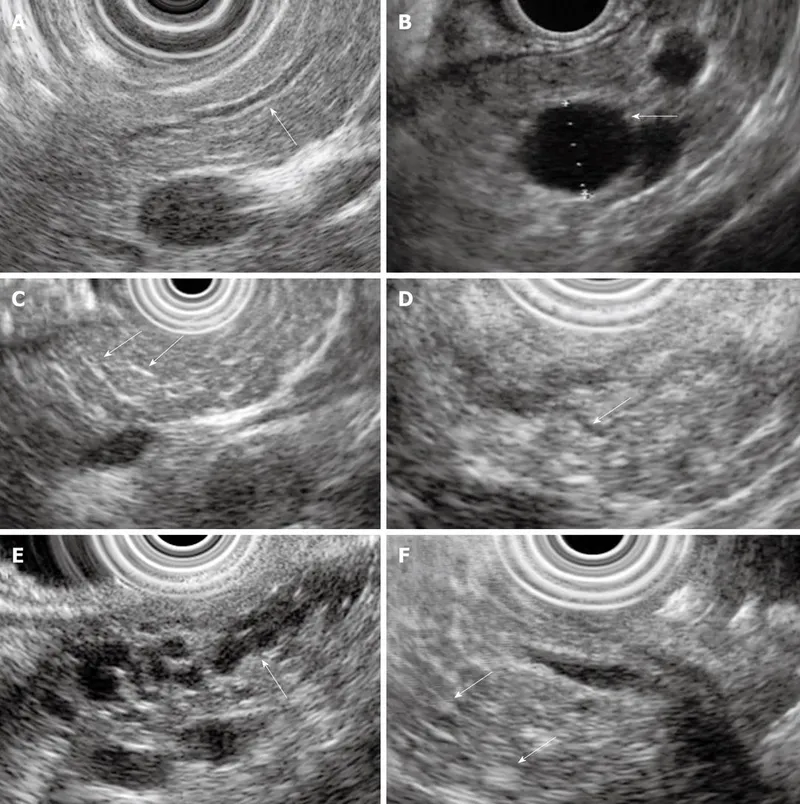

- EUS: Most sensitive for early changes (parenchymal/ductal).

⭐ EUS is the most sensitive imaging modality for detecting early changes of chronic pancreatitis.